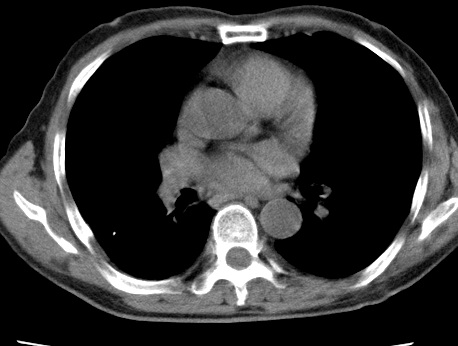

考虑右肺中叶不张,请大家发表意见

右肺中叶不张、肺门轮廓增大,占位不除外;建议增强,必要时支气管镜详查。

右肺中叶支气管闭塞,中叶肺不张,右侧肺门见肿块影。中心型肺癌的可能大。建议支气管镜检查。

右中叶体积明显缩小,且其支气管未显示,先考虑:中心型肺癌班右中叶肺不张。

建议:支气管镜检查。

考虑右肺中叶中央型肺癌并右肺中叶肺不张;建议:行纤支镜检查。

右肺门旁类圆形肿块影,右肺中叶不张,建议纤支镜检查。

1右肺门旁类圆形肿块影,右肺中叶不张,建议纤支镜检查

2右侧胸膜增厚,右侧叶间胸膜区钙化

3右肺下叶小囊状透亮影考虑肺气肿